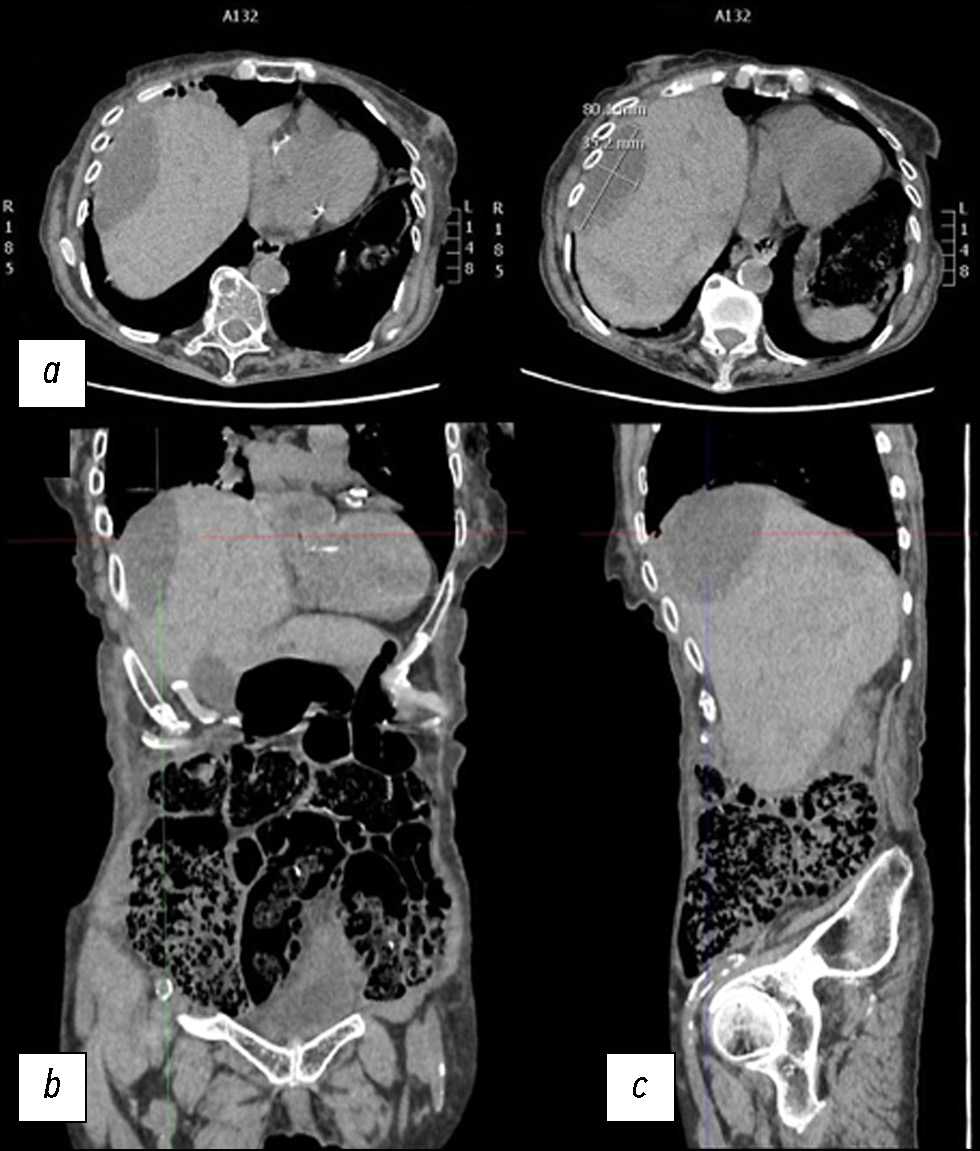

По данным УЗИ, паренхима печени была относительно неоднородной, с гипоэхогенными участками, некоторые из которых имели овальную форму. Учитывая эти данные, потребовалась КТ. Первую КТ выполняли без контрастирования, согласно требованиям отделения неотложной помощи. Кроме того, у пациентки были очень высокие показатели креатинина, что объяснялось её возрастом. По результатам первой КТ выявили несколько гиподенсных овальных участков в печени со специфическим ослаблением сигнала от жидкости (рис. 1).

Рис. 1. Снимки компьютерной томографии без контрастного усиления: a — аксиальная плоскость; b — корональная плоскость; c — сагиттальная плоскость.

На снимках в аксиальной плоскости сверху (справа, с указанием размеров), в корональной и сагиттальной плоскостях наблюдались неоднородное ослабление сигнала и увеличение печени с гиподенсными овальными образованиями и жидкостью повышенной плотности (25–30 единиц по шкале Хаунсфилда) в субкапсулярной области, самое большое из которых соответствовало VII сегменту печени и имело передне-заднюю ширину 8 см и максимальную толщину 35 мм. В брюшной полости наблюдался сопутствующий выпот.